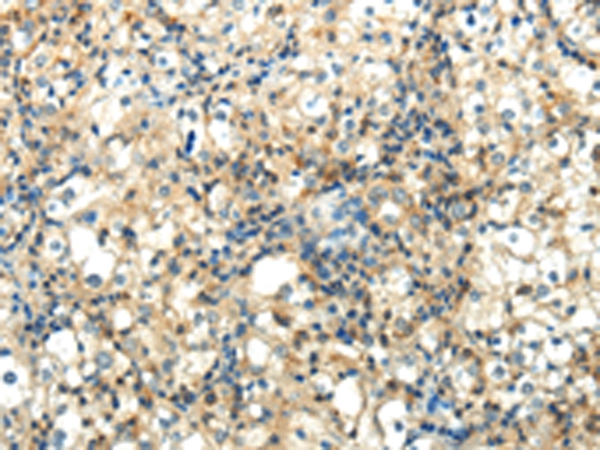

分类: 科研抗体货号: P43452别名: E2F-5应用: WB,IHC反应种属: Human,Mouse